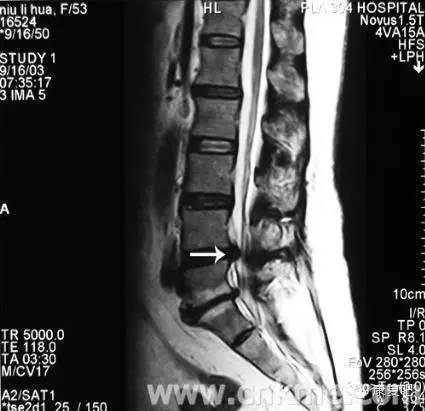

3、核磁共振攝影(MRI)

可顯示出狹窄的部位(脊髓腔的狹窄)、椎間盤(pán)物質(zhì)的突出進(jìn)入脊髓腔、或受侵害之脊髓神經(jīng)根。